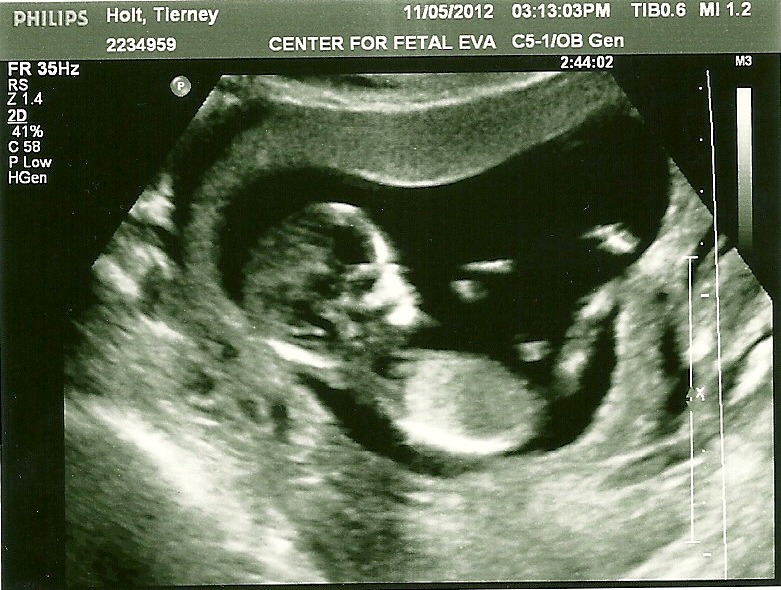

And of course the absolute best part of my week, seeing our precious little guy, and hearing that he's healthy and all is well.

I think he's definitely going to have Shane's nose, but Shane says otherwise.

Confirmation that he is in fact still a boy!